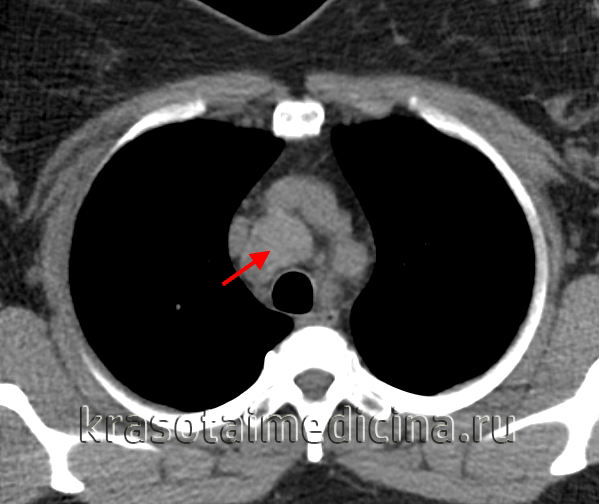

(б) У этой же пациентки при КТ с контрастным усилением визуализируется крупный мягкотканный конгломерат, включающий в себя преваскулярные, паратрахеальные лимфатические узлы и лимфатические узлы корней легких. Следует отметить наличие умеренного плеврального выпота справа, альвеолярной инфильтрации и узелков в правом легком, что соответствует вовлечению в опухолевый процесс легкого. (а) У этой же пациентки при ФДГ-ПЭТ/КТ определяется повышенный уровень поглощения ФДГ различными лимфатическими узлами средостения и корней легких. Следует отметить накопление ФДГ паренхимой легкого, что свидетельствует о вовлечении его в опухолевый процесс. Также обращает на себя внимание интенсивное поглощение ФДГ подмышечными лимфатическими узлами с обеих сторон.

(б) Молодой мужчина с лимфомой Ходжкина. При КТ с контрастным усилением в переднем средостении визуализируется объемное образование гетерогенной структуры с дольчатым контуром. В структуре образования выявляются отдельные зоны пониженной плотности, соответствующие зонам некроза. (а) Пациент с нодулярным склерозом при лимфоме Ходжкина. На совмещенных изображениях при КТ с контрастным усилением определяются объемное образование в переднем средостении, инвазия перикарда с облитерацией субэпикардиальной жировой клетчатки и небольшой плевральный выпот слева.